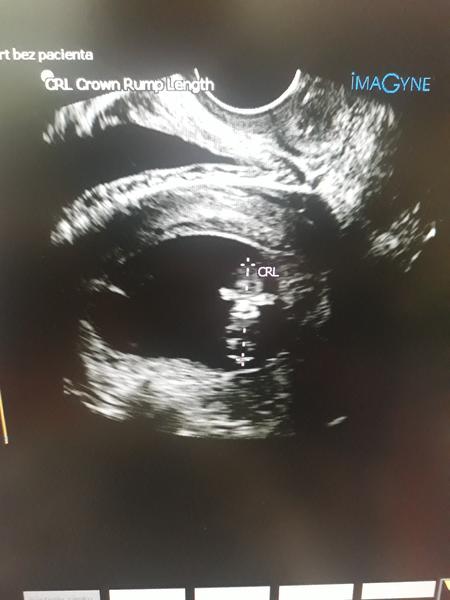

No strašne to uteká veru ❤️ My zatiaľ pohlavie nevieme ale strašne som zvedavá co to bude ale to je v podstate jedno hlavne nech je v poriadku ❤️ Ale ja mám tušenie ze to bude opäť dievčatko 🙂 fotecky som dávala minule z 13 tt a v pondelok mám ďalšiu kontrolu tak som zvedavá 🙂 zatiaľ je všetko ako ma byt ani ťažkosti zatiaľ nemám žiadne ... tak to som rada ze ste v poriadku a pekne rastiete ;)